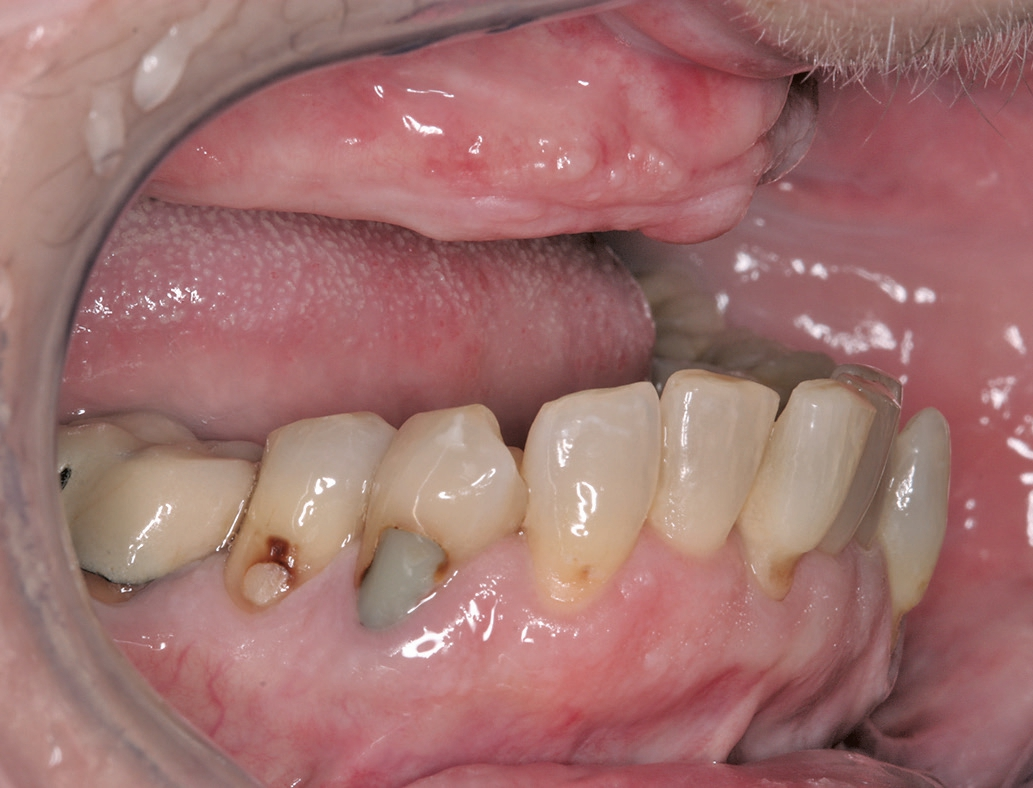

Der vorliegende Fall legt die Oberkiefer- Rehabilitation einer 66 Jahre alten Patientin dar (Abb. 1 u. 2). Diese wünschte sich eine hochwertige Lösung auf Implantaten. Die Versorgung des Unterkiefers wurde im Rahmen der ganzheitlichen Sanierung von uns ebenfalls geplant. Allerdings entschied sich die Patientin aufgrund der noch ausreichenden Passung der bestehenden Prothetik und auch aus Kostengründen, diese Versorgung zunächst noch zurückzustellen.

Wichtig sind bei dieser Art der Versorgung die exakte Planung der Behandlungsschritte und eine ideale Zusammenarbeit zwischen dem Oralchirurgen/Implantologen, dem behandelnden Zahnarzt und dem Labor. Im vorliegenden Fall fiel die Wahl auf einen im CAD/CAM-Verfahren industriell gefrästen Steg, da das Materialgefüge homogen ist und ein Steg bei sorgfältiger Übertragung der Mundsituation auf die Arbeitsmodelle mittels Abformung und Bissregistrierung eine präzise Passung sowie einen spannungsfreien Sitz sicherzustellen vermag. Mithilfe der CAD/CAM-Technologie haben wir die Möglichkeit, den Patienten eine äußerst präzise und langzeitstabile prothetische Lösung anzubieten und dennoch die Kosten in einem überschaubaren Rahmen zu halten. Die präimplantologische Behandlung bestand in der Sanierung insuffizienter konservierender UK-Versorgungen und einer Parodontalbehandlung, um mögliche Infektionsquellen am Restzahnbestand zu entfernen. Während der gesamten Behandlungsdauer trug die Patientin die alte Totalprothese weiter, unterbrochen von entsprechenden Karenzzeiten während der Heilungszeiten.